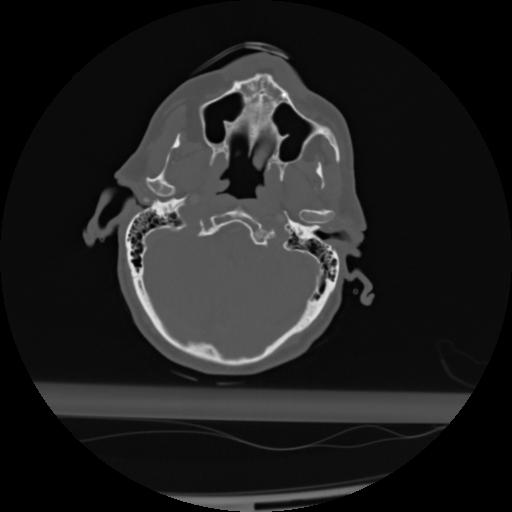

21 ANGIO,CE,Axial,3.0,ANGIO,,